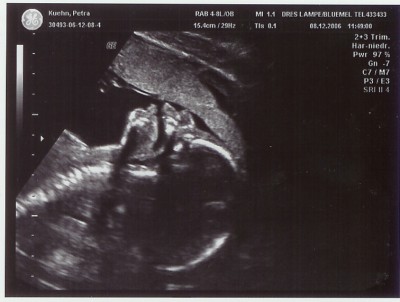

Und für Tunnelgrabungen ist dein Zwerg wohl noch etwas früh dran, oder nicht?!